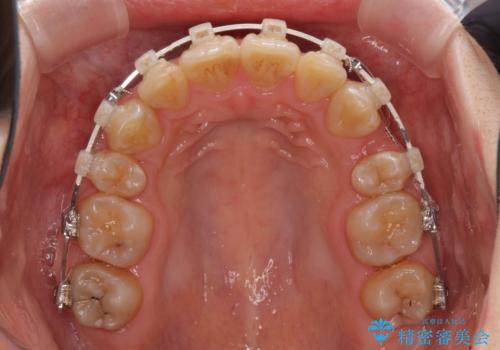

- 矯正装置

- 審美装置

- 治療計画

- 口元の閉じにくさと、前歯のでこぼこの歯並びを気にして来院された患者様です。

口元を積極的に引っ込めるために、上下左右の小臼歯計4本を抜歯することとしました。

咬み合わせが深く、咬合力強いため、補助装置を使用しながら積極的に口元を下げることとしました。